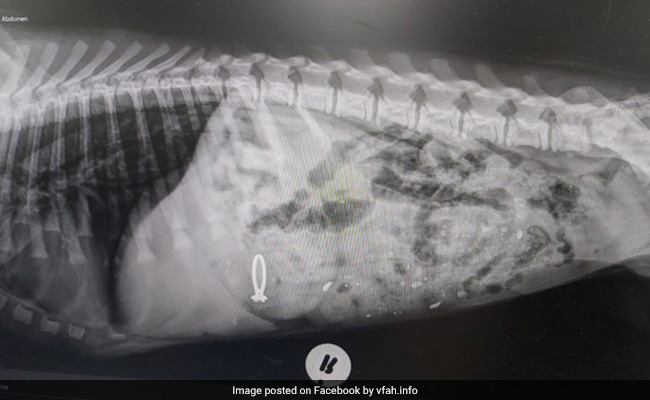

Dog Swallows Engagement Ring { All News 'Dog Swallows Engagement Ring' - 1 News Result(s) Dog In South Africa Swallows Owner's Engagement Ring Sunday February 9, 2020 Offbeat | ANI A pooch from South Africa seems to have a liking for expensive cuisine, even if it is ideally not meant to be eaten. www.ndtv.com Share Twitter WhatsApp Facebook Reddit Email 'Dog Swallows Engagement Ring' - 1 News Result(s) Dog In South Africa Swallows Owner's Engagement Ring Sunday February 9, 2020 Offbeat | ANI A pooch from South Africa seems to have a liking for expensive cuisine, even if it is ideally not meant to be eaten. www.ndtv.com Share Twitter WhatsApp Facebook Reddit Email